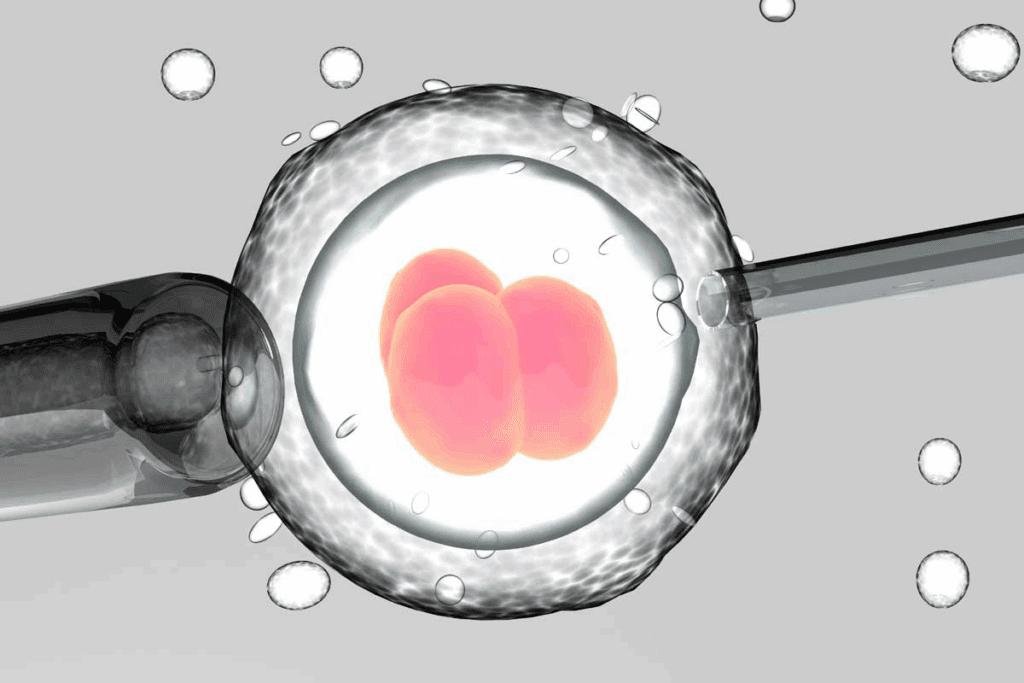

In vitro fertilization is a medical technique in which a woman’s eggs are retrieved from her ovaries, fertilised with sperm in an external lab dish, the resulting embryos are cultured for 3-5 days and then one or more healthy embryos are transferred into the uterus to achieve pregnancy. Intracytoplasmic sperm injection (ICSI) is a specialised form of IVF treatment. It involves injecting live sperm into an egg through an artificial process. After fertilization, it forms an embryo. ICSI is most frequently used by medical professionals when a patient’s ability to conceive is impacted by male infertility.

Intracytoplasmic Sperm Injection (ICSI) is a specialised form of In Vitro Fertilisation (IVF) which is used to treat severe male factor infertility. ICSI is typically recommended when there is a low sperm count, a high number of sperm with aberrant shapes, decreased sperm count, no sperm in a semen analysis, or after an unsuccessful vasectomy reversal. It is also recommended for couples who have a history of multiple IVF failures or no fertilization.

The key difference between ICSI and IVF is how sperm and eggs are fertilized. ICSI involves injecting a single mature egg with a single sperm for fertilization. In conventional IVF, a plate containing the eggs is filled with many sperm. To allow the sperm to naturally penetrate the egg, the sperm and eggs are kept together for a while. Couples who have trouble conceiving because of male factors or who have not had success with traditional IVF are advised to consider ICSI.

After egg retrieval, the eggs are fertilised with sperm in the laboratory.

- Fertilisation takes place in a controlled environment

- The resulting embryos are carefully monitored for 3–5 days